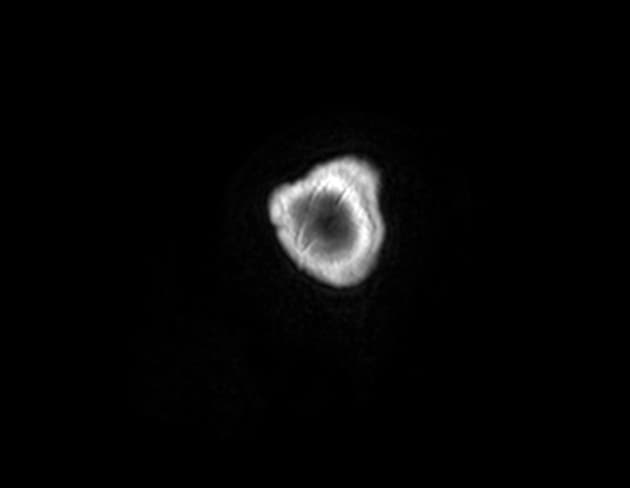

- Tổn thương cho thấy hạn chế khuếch tán (restricted diffusion) với tín hiệu tăng trên hình ảnh khuếch tán (DWI) và tín hiệu giảm trên bản đồ ADC.

- Phổ cộng hưởng từ (MR spectroscopy) của tổn thương thùy thái dương phải cho thấy đỉnh lipid/lactate tăng rõ rệt, đồng thời giảm N-acetyl aspartate (NAA), creatine (Cr) và choline (Cho). Vùng não lân cận có phổ cộng hưởng từ chủ yếu bình thường, chỉ tăng nhẹ choline.

- "Áp xe thùy thái dương có thể phát triển như một biến chứng của viêm xương sọ đáy, với các đặc điểm điển hình trên cộng hưởng từ như viền ngấm thuốc, hạn chế khuếch tán và phổ cộng hưởng từ bất thường với đỉnh lactate/lipid tăng cao."

- "Phổ cộng hưởng từ giúp phân biệt áp xe với u: áp xe thường cho thấy đỉnh lactate và lipid nổi bật, giảm NAA, Cr và Cho; trong khi u thường tăng choline và giảm NAA."